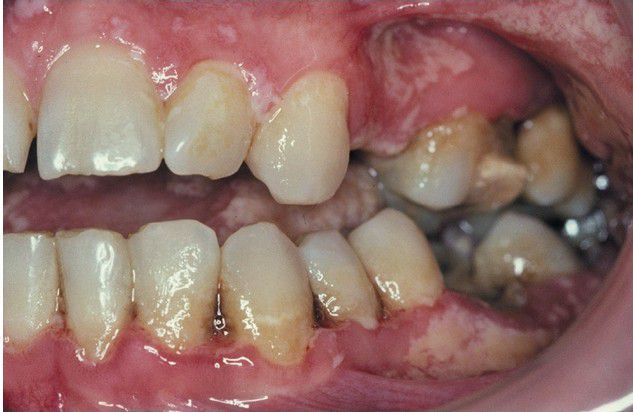

Multiple punched-out interdental papillae of the mandibular gingiva. Note diffuse pseudomembranous candidiasis of the surrounding mucosa.